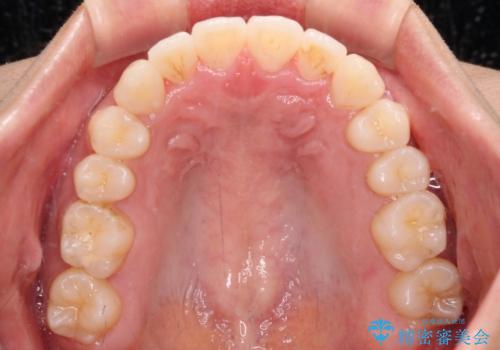

捻れた前歯をできるだけ短期間で 表側のワイヤー矯正

- 上下前歯のねじれを気にして来院された患者様です。

ワイヤー矯正でもマウスピース矯正でも対応可能でしたが、マウスピース矯正の自己管理が面倒であること、上顎前歯の捻転が著しいことから、ワイヤー矯正での治療を希望されました。

日々前歯の捻れが解消されていくので、歯の動きを楽しみながら矯正治療を進めることができました。